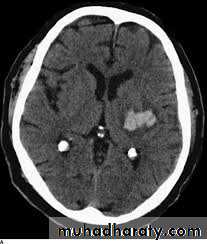

• Usually due to a ruptured intracranial aneurysm or less commonly an arteriovenous malformation.• CT is the best initial investigation to diagnose.

• A subarachnoid haemorrhage is recognized by high density blood in the cortical sulci, Sylvian fissures and basal cisterns.

• CT will also show any intracerebral haemorrhage or blood in the ventricles

• An unenhanced routine head CT is followed by CT angiography as a single investigation to diagnose subarachnoid haemorrhage, localize the bleeding and demonstrate the aneurysm.Head injury